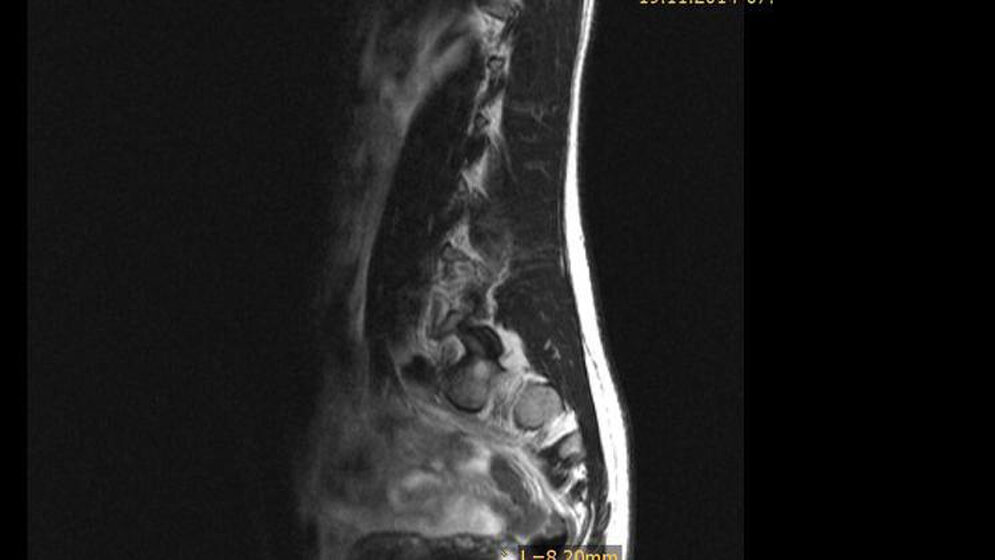

Die Ovula Nabothi sind häufig vorkommende gynäkologische Veränderungen, in der Größe variabel. Sie kommen einzeln oder multipel vor. Es kann problematisch sein, sie von einem minimal-invasiven Karzinom zu differenzieren. Die genaue Kenntnis der histologischen Charakteristika ist wichtig, um eine Fehldiagnose und Übertherapie benigner Veränderungen zu vermeiden.